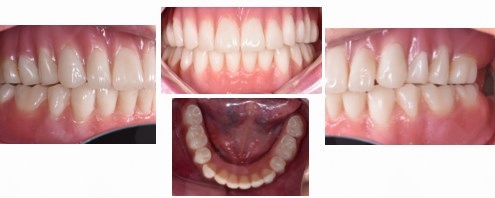

Los implantes dentales son la forma mas estética y funcional de sustituir una diente perdido, ya sea por caries, enfermedad periodontal, traumatismo o agenesia. Lo mas importante para que este tratamiento sea exitoso es su correcta planeación.